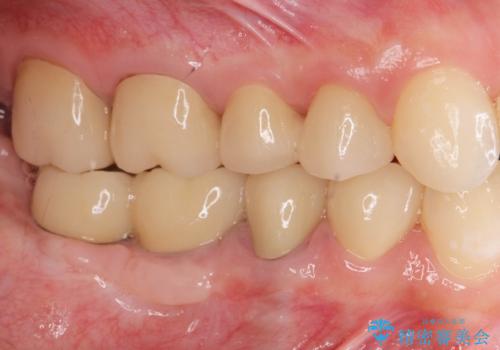

虫歯や咬合関係・歯槽骨の吸収・根尖病変・歯の欠損・複合的な問題を一つずつ解決し、

安定した噛み合わせの構築・歯ブラシのしやすい環境の整備・歯内歯周の感染除去・造骨を伴うインプラント治療

を行い、長期的な予後を見込める口腔内環境を確立、整備して行きます。